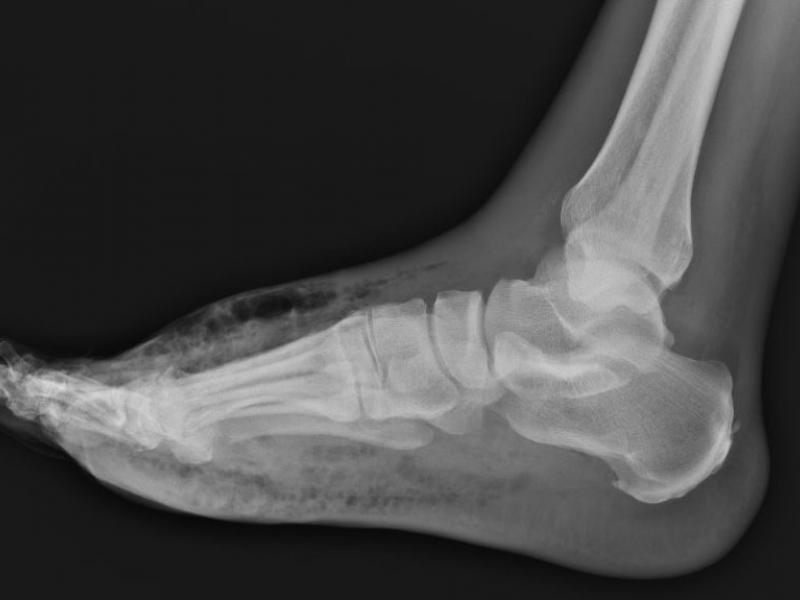

What's the diagnosis? By Dr. Katie Selman